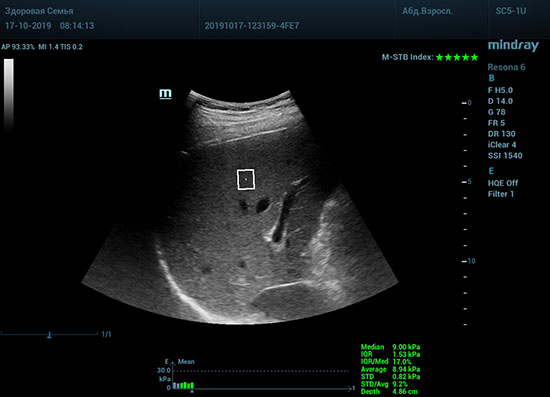

Что может дать ультразвуковое исследование печени помимо образований, гепатомегалии и цирроза? Диагностические системы, оснащенные функцией STQ (SoundTouchQuantification) имеют возможность регистрировать сдвиговые волны в паренхиме печени и оценить её эластичность. Такие возможности есть у систем серии Resona 6 и Resona 7 компании Mindray.

Определение плотности печени. Не ошибся ли оператор при измерении эластических свойств печени? Для оценки критериев качества предусмотрен индекс MBT, который покажет насколько «твердой» была рука оператора и двигалась ли печень. При MBT 5* рука тверда и показатели достоверны. Для оценки качества результатов используется IQR индекс, отображающий колебания показателей в точке измерения при расчете медианы. Показатели при IQR <30% считаются приемлемыми. Техника сканирования через межреберные промежутки требует размещение окна интереса на несколько сантиметром ниже капсулы, для исключения эффекта реверберации. Установка ROI на паренхиму без захвата сосудов, для исключения погрешностей измерения.

Стадия фиброза определяется по системе METAVIR Staging, построенной на данных биопсии и сопоставлении с данными эластографии. Своевременная диагностика фиброза, и начало его лечения, залог благоприятного исхода заболевания.